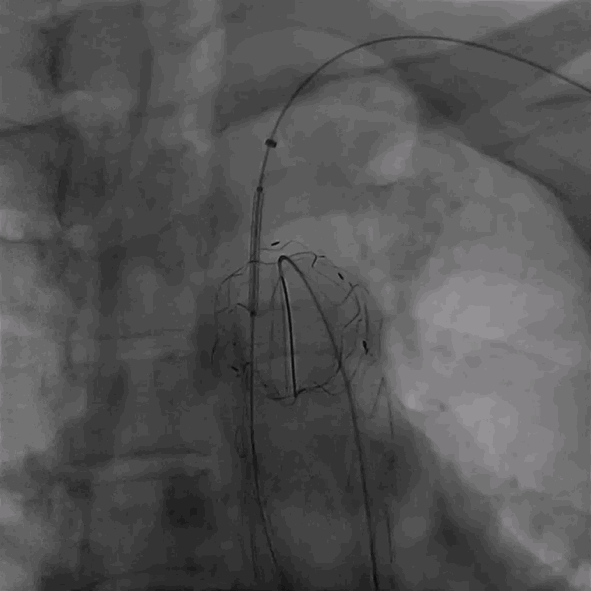

植入华脉泰科覆膜支架

释放华脉泰科支架前三节,再次造影确认位置